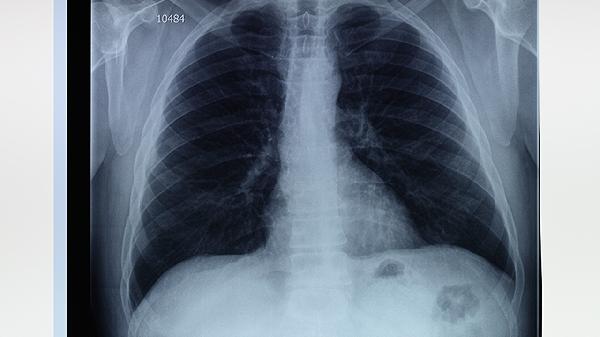

3、预防肺气肿和肺大泡的关键在于戒烟、避免空气污染和职业暴露。戒烟是预防和治疗肺气肿和肺大泡的最有效措施,戒烟后肺部功能会逐渐改善。避免空气污染和职业暴露于有害气体和颗粒物,可以减少肺部损伤。定期进行肺功能检查和胸部影像学检查,有助于早期发现和治疗肺气肿和肺大泡。

4、肺气肿和肺大泡患者应定期监测肺癌风险,特别是长期吸烟者。定期进行低剂量CT扫描,有助于早期发现肺癌。保持健康的生活方式,如均衡饮食、适量运动和避免二手烟,有助于降低肺癌风险。